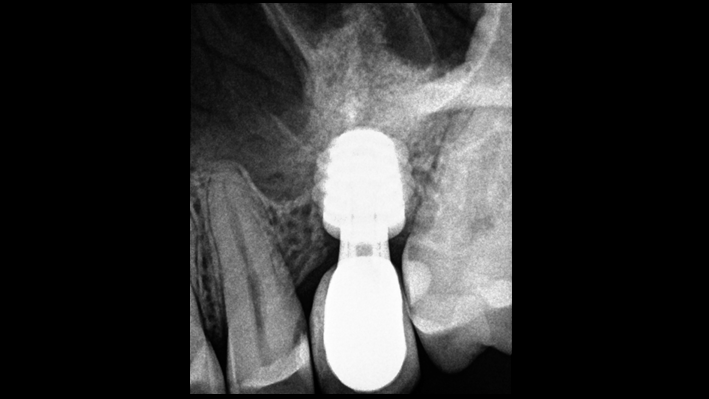

Clinical case: # 46 implant placement & GBR using i-Gen membrane for significant vertical resorption & mixed bone defect

- Courtesy of Dr. Iulian Filipov, Romania -

Keywords

AnyRidge, mandibular posterior, i-Gen, resorption, bone defect, bone regeneration, space management, #46, GBR, Dr. Iulian Filipov

Products:

AnyRidge implant system, i-Gen

“AnyRidge KnifeThread achieves excellent stability in regenerated bone & even in only 3mm bone height!”